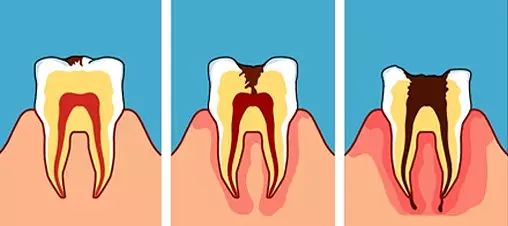

用一个简单的流程来解释,牙龈为什么会起脓包。

口腔细菌

↓

蛀牙/折断牙

影响牙神经

牙神经坏死

牙神经感染

炎症影响牙根周围的骨头

牙根周围组织化脓

脓水没有地方发泄

脓水穿透骨头冲到牙床

肿胀

肉眼见到牙龈起脓包

为了方便理解,已经给你配好了图。